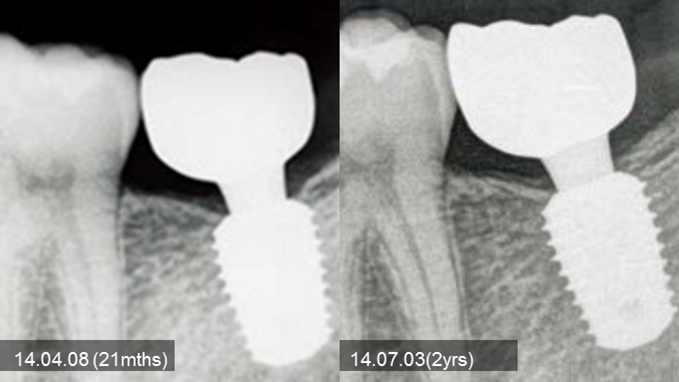

Clinical case: Bone growth in deepest thread of 8.0mm AnyRidge fixture

- Courtesy of Dr. Kwang Bum Park -

Clinical case: Bone filling into the bottom of deepest thread at 8.0mm AnyRidge fixture

Keywords

AnyRidge, Knifethread ,extraction socket, ,initial stability ,Allograft, ,osseointegratio ,Dr. Kwang Bum Park, , Mandibular, Single replacement, AnyRidge, Mega-oss,

Products used

Implant system-AnyRidge, Regeneration-Mega-Oss